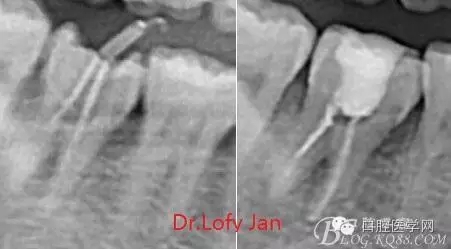

前言:自己做的一些曲面斷層片在未試尖根管治療中的病例整理,發(fā)現(xiàn)問題很多包括自身的,技術(shù)的,還有設(shè)備的問題,予以總結(jié)整理并期待進(jìn)一步提高。

根管治療術(shù)是牙體牙髓疾病治療中最復(fù)雜和最關(guān)鍵的治療項目。根管充填材料抵達(dá)根尖、并能嚴(yán)密堵塞根尖孔,是確保根管治療效果的關(guān)鍵指標(biāo)。為了保證根管充填到位,醫(yī)生需要在術(shù)前照牙片以了解牙根根管的數(shù)量、彎曲程度和長度,在術(shù)中有時需要插針照牙片來精確測量根管長度,術(shù)后必須照牙片以確定是否根管充填到位,如果欠填或超填,就需要重新充填、重新照牙片確認(rèn),直到根管充填到位。所以,在患者接受根管治療時有時會反復(fù)照牙片。

《數(shù)字化根尖片、曲面斷層片、CBCT測量牙齒長度準(zhǔn)確性的比較研究》文中顯示:平行投照數(shù)字化根尖片影像長度和牙齒實際長度之間無顯著性差異(P0.05);數(shù)字化曲面斷層片影像長度和牙齒實際長度之間有顯著性差異(P0.05),平均失真率為17.05%。CBCT冠狀面測量結(jié)果中除上頜前磨牙區(qū)、下頜前磨牙區(qū)與真實長度差異無統(tǒng)計學(xué)意義(P0.05)外,其余6個分區(qū)差異均有統(tǒng)計學(xué)意義(P0.05);矢狀面測量結(jié)果中上頜磨牙區(qū)、下頜磨牙區(qū)、下頜前磨牙區(qū)、下頜尖牙區(qū)、下頜前牙區(qū)與真實長度比較差異均有統(tǒng)計學(xué)意義(P0.05)。結(jié)論平行投照數(shù)字化根尖片較曲面斷層片和CBCT能更加精確地反映牙齒的真實長度。

病例分析:曲面斷層片在x線輔助診斷與檢查中目前大多數(shù)文獻(xiàn)和著作都建議只能作為初診拍片檢查手段,不能作為終末疾病的確診與手術(shù)療效的評價指標(biāo),臨床大部分中小型門診都因為設(shè)備不齊全導(dǎo)致信息偏差很大。